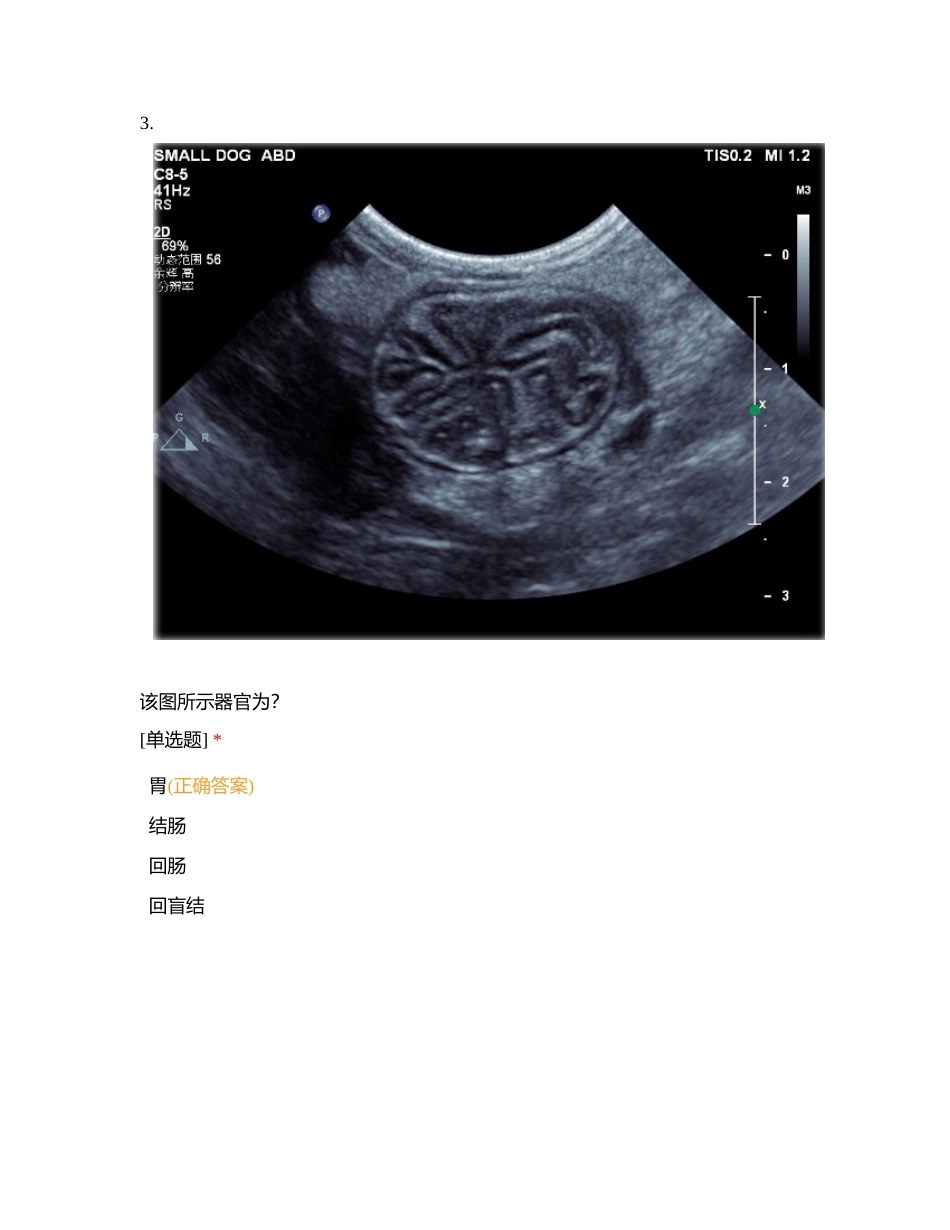

梅奥宠物医学中心-胃肠超声影像在线侦测[复制]您的姓名: [填空题] *_________________________________1. 关于兽医临床胃肠道超声检查,以下说法正确的是? *受检动物需禁食 12 小时(正确答案)可以给予灌...